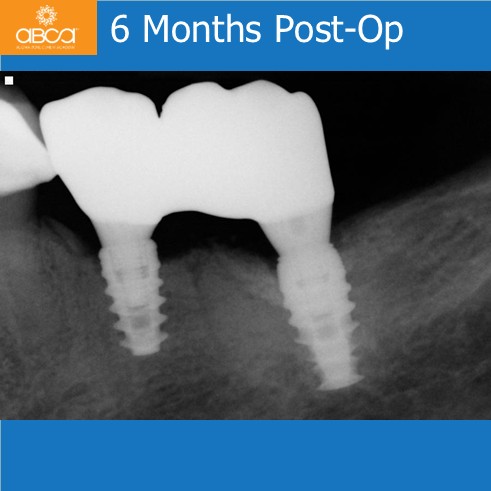

The patient presented with an infected and fractured molar with compromised buccal plate. The extraction was done in segments. Osteotomy prep grafted with Bond Apatite®, uncover osteotomy, immediate implant placement. Note the keratinized gingiva around the healed implant. The key here was no flap at the time of the extraction.